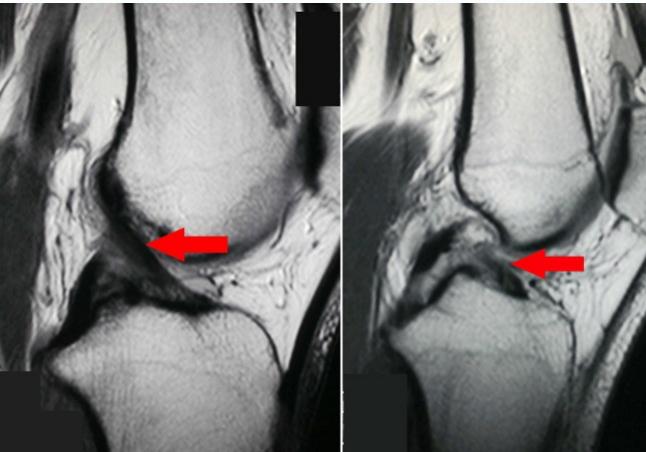

MRI

- Best imaging modality for PCL injuries